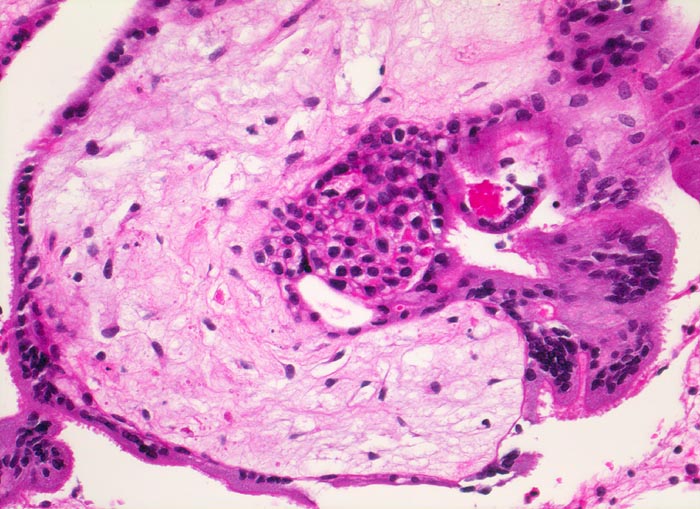

Abortkurettage: choriales Gewebe

Gefässe sind im degenerierten Zottenstroma nicht sicher zu erkennen. Die Zotte wird bedeckt von fokal leicht proliferiertem Zytotrophoblast und mehrkernigem Synzytiotrophoblast.

Missed abortion in der 11. Schwangerschaftswoche, sonographisch entsprechend der 9. Schwangerschaftswoche.